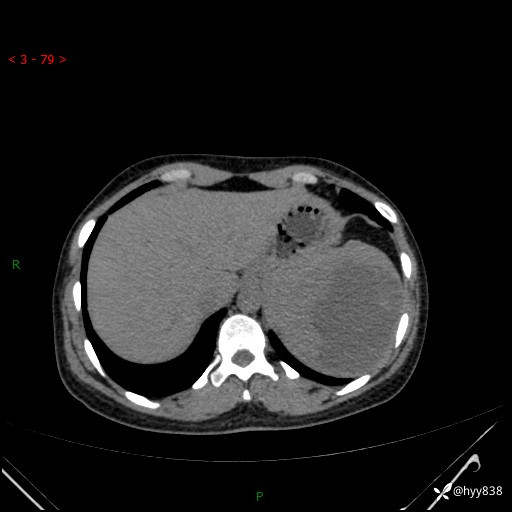

患者性别:男

患者年龄:44岁

主诉:外院超声发现脾脏占位,来我院进一步诊治。

辅助检查:CT

临床诊断:脾脏占位

脾脏CT平扫+增强(动脉期+静脉期)